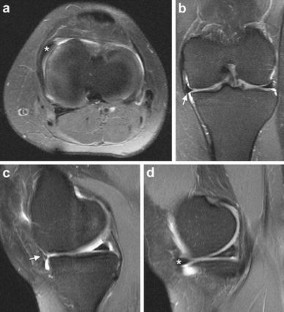

Fig. 4